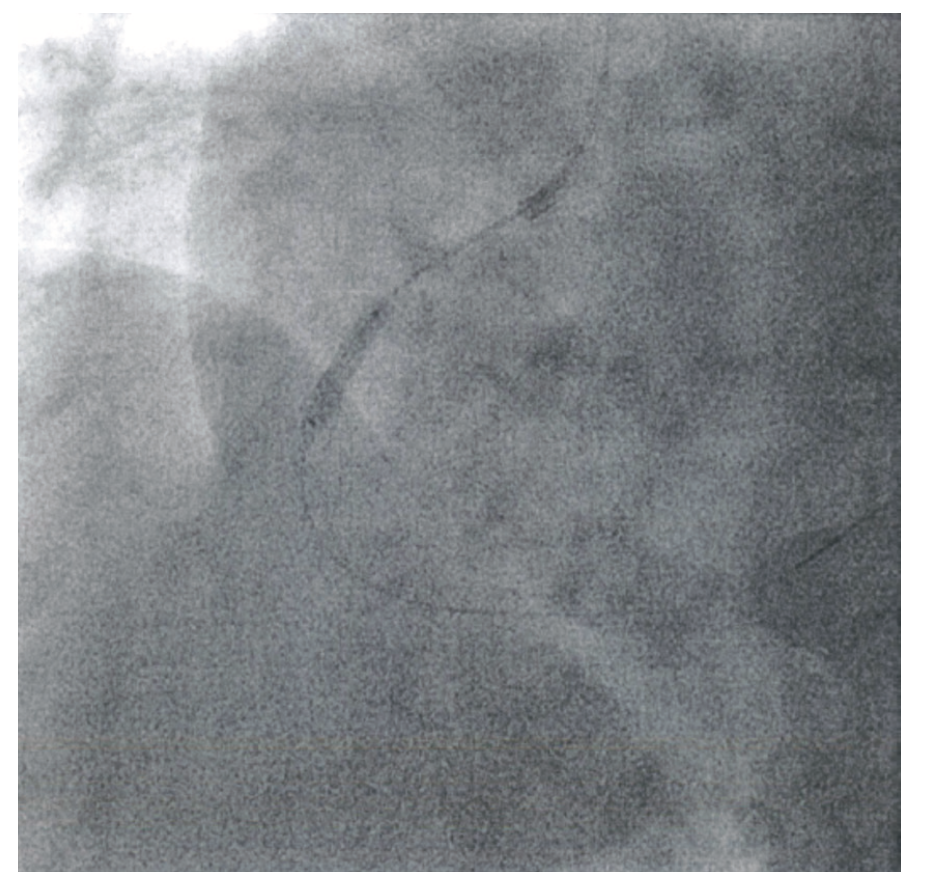

However, the right coronary artery (RCA) had a tight 80%-90% mid stenosis and a 100% occlusion distally. She underwent percutaneous coronary intervention of the RCA with successful cannulation of the distal RCA followed by a 3.5 mm drug-eluting stent (DES) placement. The mid RCA was also treated and stented with a 3.5 mm DES. However, the proximal segment of the mid-RCA stent could not be fully expanded despite high-pressure inflations. Another 3.5 mm DES was inserted to fully cover the proximal portion of the lesion, with high-pressure dilatations using noncompliant (NC) 3.5 mm and NC 3.75 mm balloons. High pressures of 20-24 atmospheres could not dilate the stent, because of the ring of calcium in the deep layers of the artery (Figure 1). A 4.0 mm NC balloon could not cross. The procedure was terminated. Surgical consult was obtained, but the patient was deemed high risk because of concomitant carotid artery stenosis and recent stroke. Therefore, it was decided to bring her back and try Shockwave therapy (IVL).